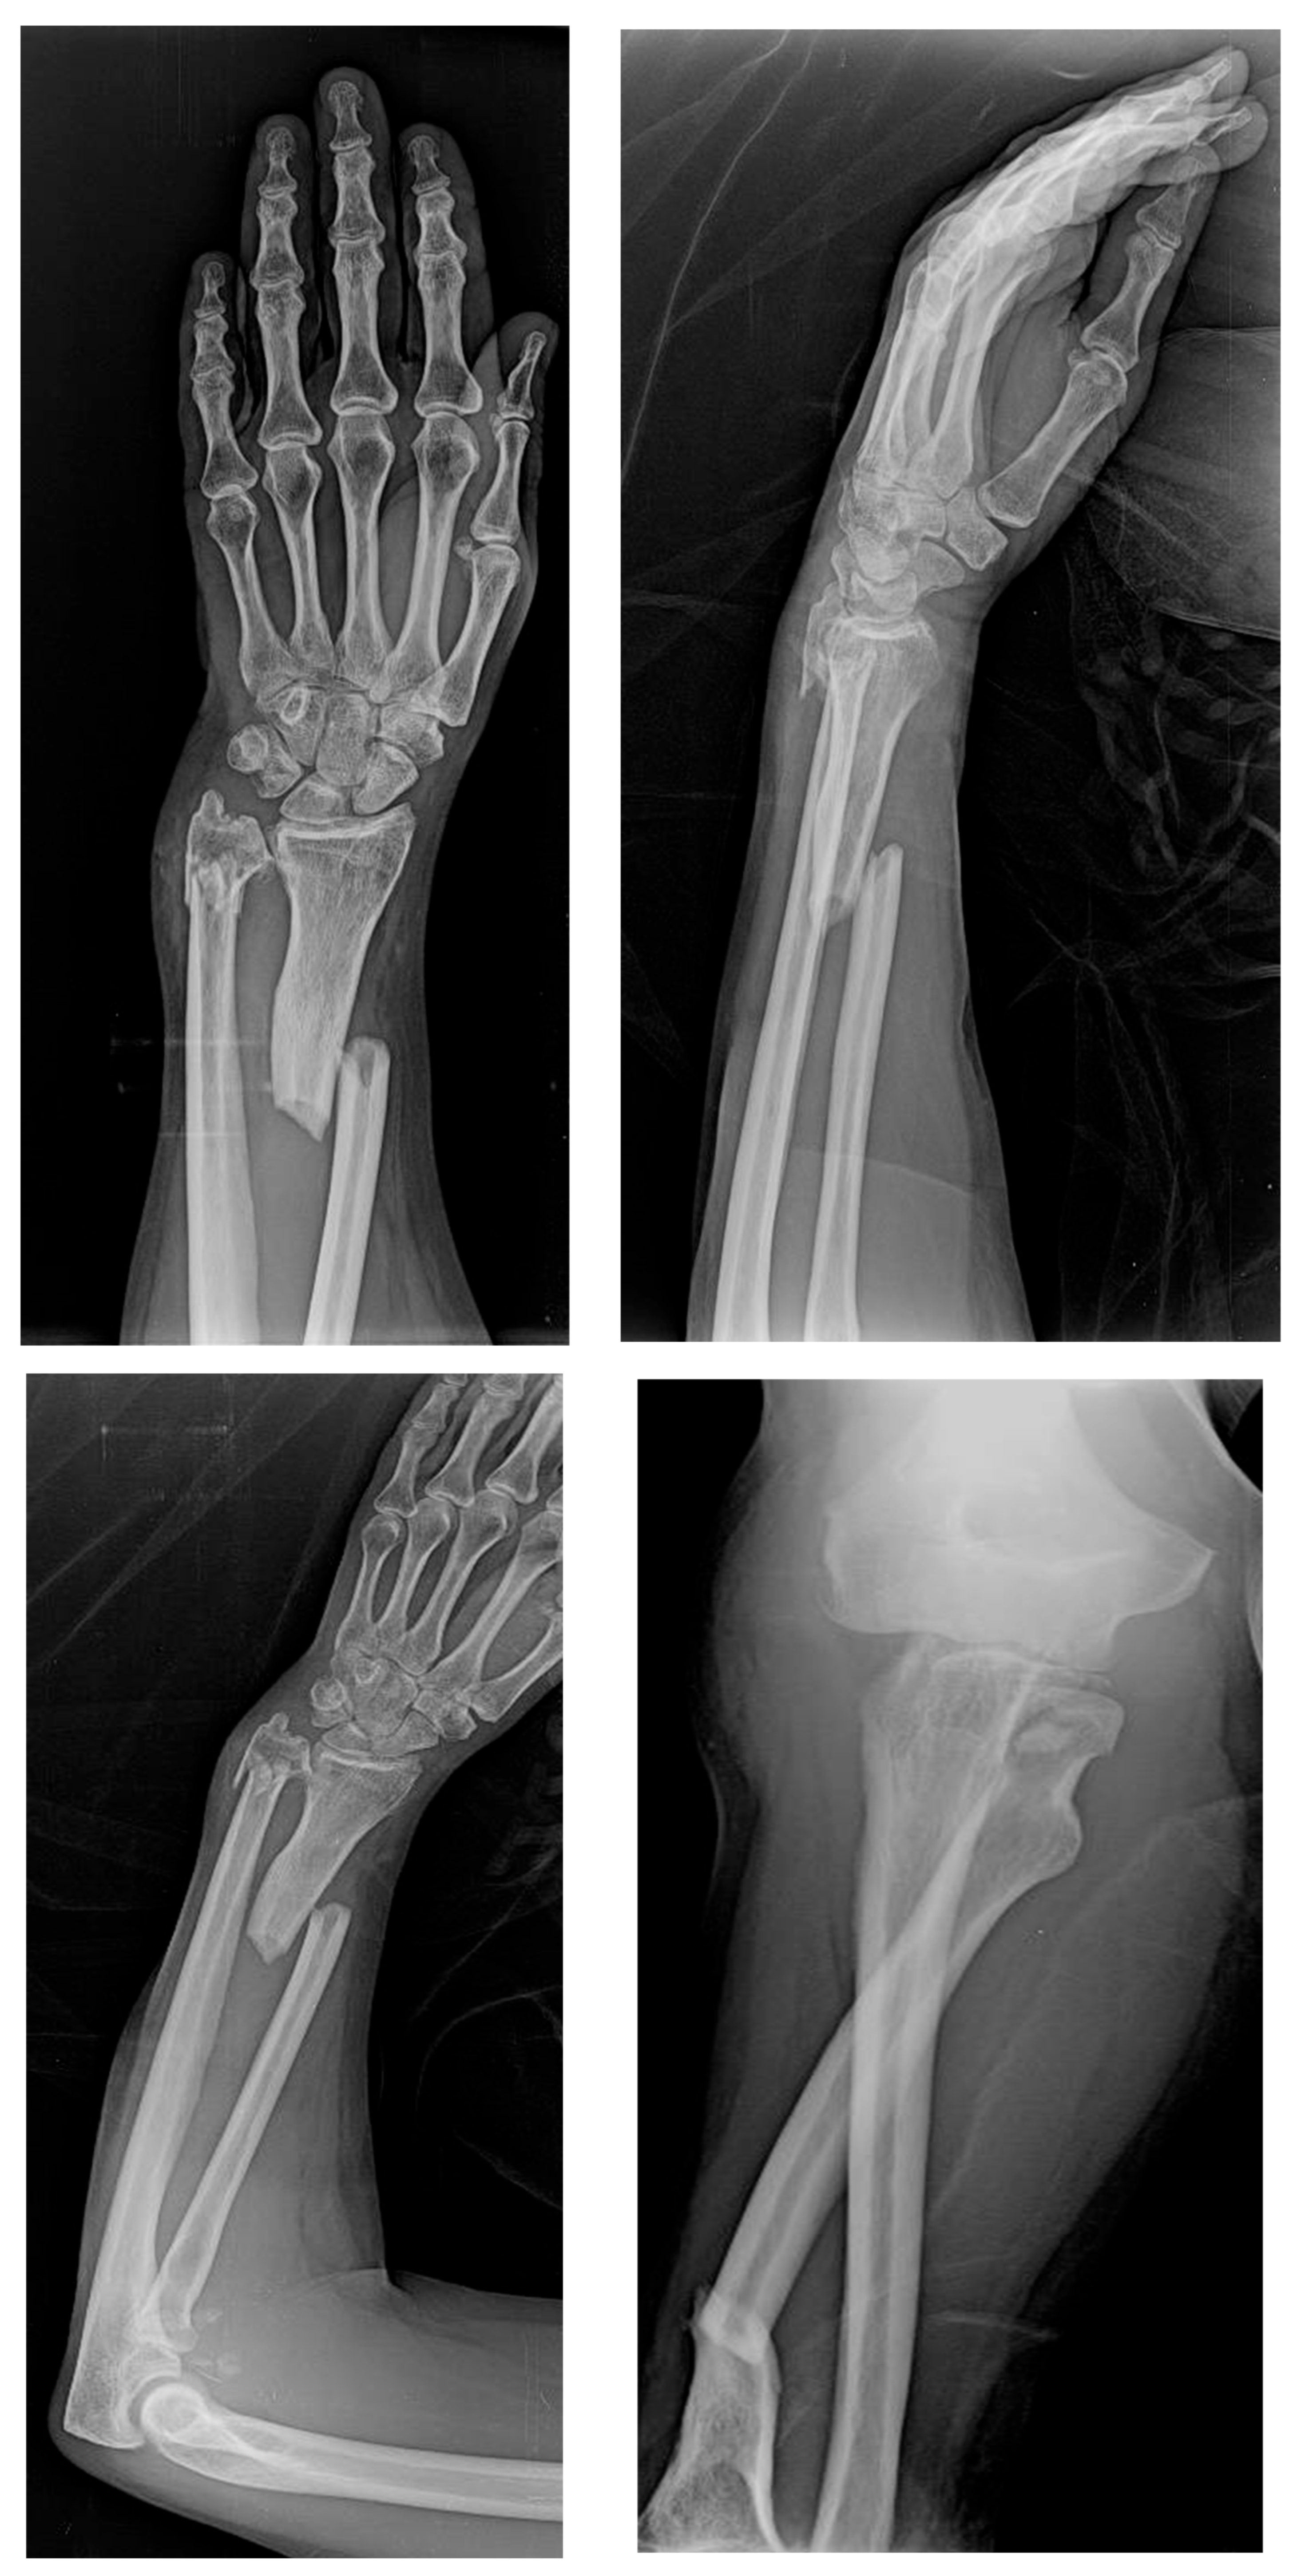

The following day, the patient underwent surgical intervention. The procedure included open reduction and internal fixation (ORIF) of the radial fracture using an anatomical locking plate, as well as closed reduction and intramedullary fixation of the ulnar fracture with a Steinmann pin. Given the extent of the radial head fracture, a prosthetic radial head replacement was performed. Ulnar collateral elbow ligament reconstruction was also carried out to restore elbow stability. Intraoperative assessment confirmed the integrity of the distal radioulnar joint (DRUJ), although there was partial damage to the interosseous membrane, which was carefully addressed during surgery (Figure 3).

Figure 3. Postoperative follow-up X-rays.